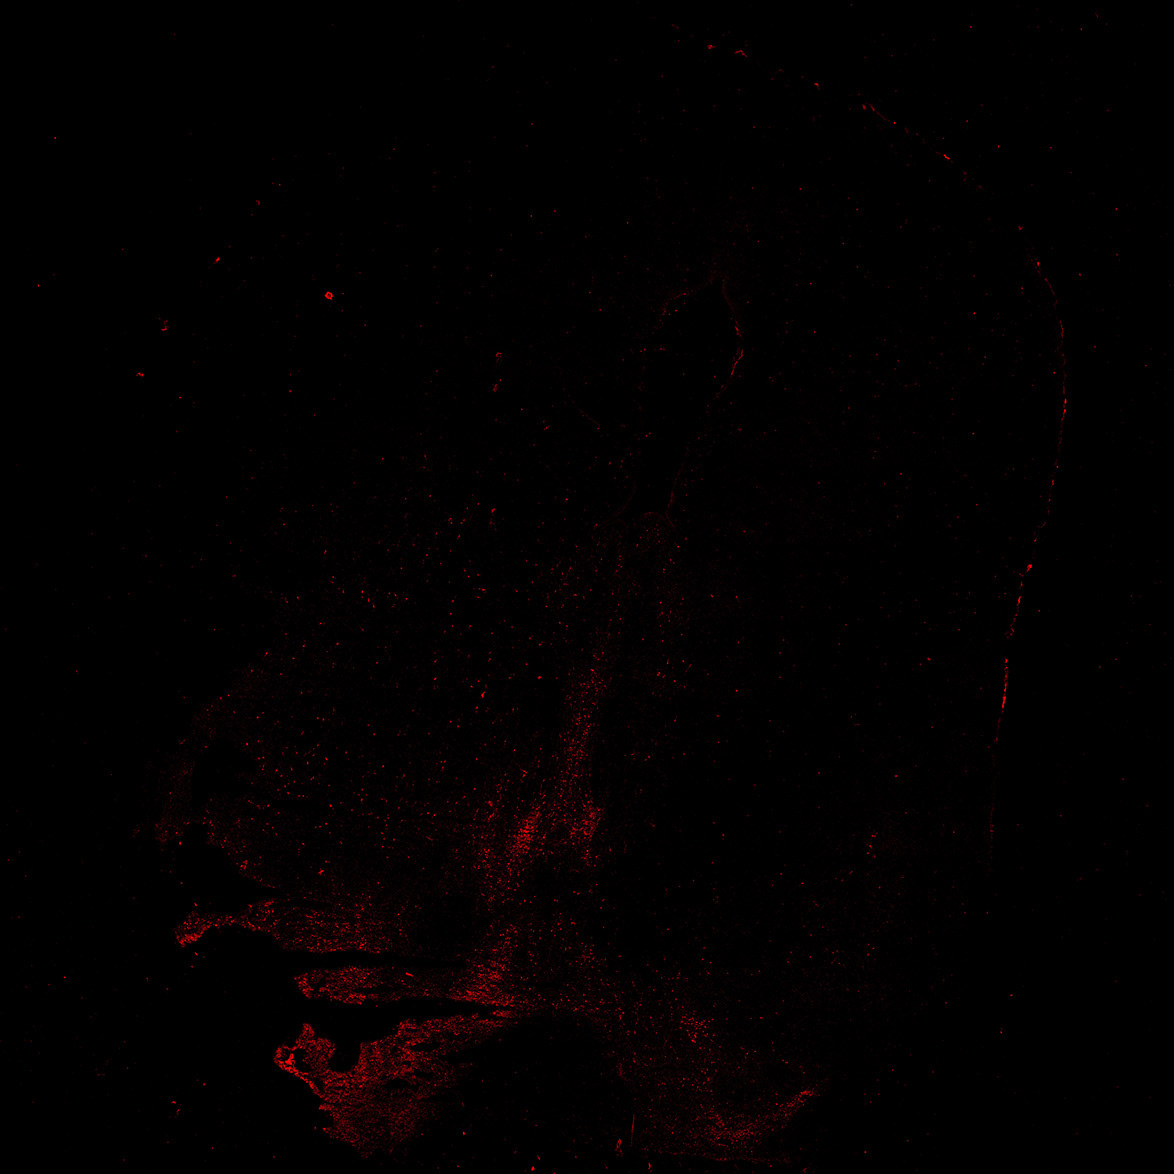

TH

6PCW human midbrain